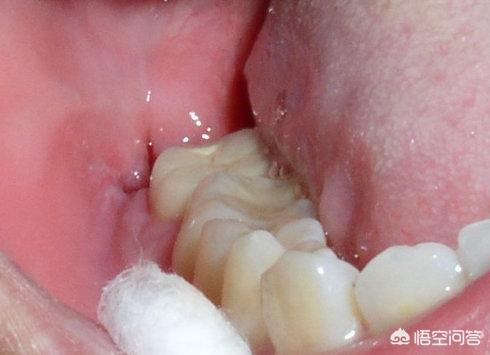

其实拔完智齿创口会微痛是正常现象,术后创口大的可能会有炎症,需要吃甲硝唑和布洛芬进行消炎止痛,如果体内免疫功能较弱,拔完张口受限严重,得进行输头孢治疗,一旦头晕出现低烧,还得输葡萄糖提高抵抗力,痛感两天逐渐好转,一周后就不会疼。

1、说明牙槽窝内可能受到致病菌感染,并且创口空虚感强烈,你可以看到血凝块颜色变得异常,灰白色腐败臭味难闻,这些都是干槽症,原因是手术创伤大,牙槽窝也大。

2、除了创口痛,干槽症牵引到头痛才最难受,要注意缝合伤口,减少细菌感染的风险,一周后再去拆线,可能还会有牙洞要注意清水漱口,这时的创口已经不会痛,想要避免干槽症,拔智齿最好到医院做微创拔除手术,这样出血也不会过多。